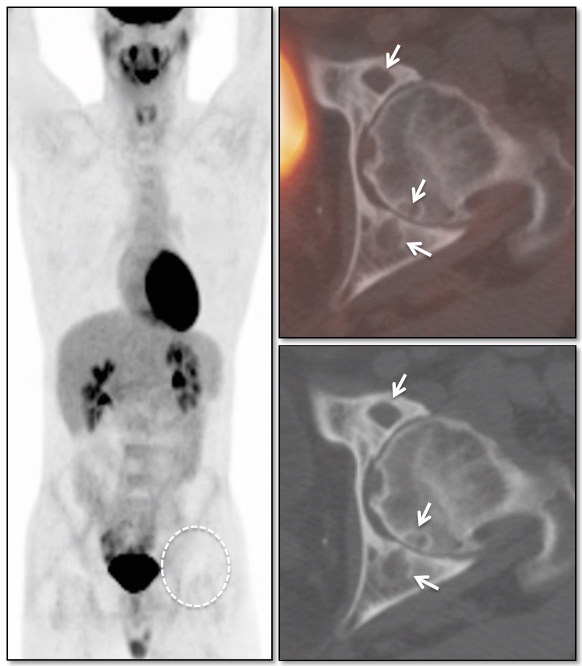

Schmorl’s Node:

A Schmorl’s node is a focal herniation of disc material into a vertebral body. It appears as a rounded lucency in the vertebral body, contiguous with its endplate. The lucency often demonstrates surrounding sclerosis.

While typically non-avid, Schmorl’s nodes can be FDG-avid, occasionally demonstrating even intense metabolic activity. MRI evaluation may occasionally be required to distinguish a hypermetabolic Schmorl’s node from a lytic metastasis.